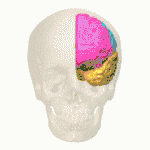

Neurons located in different structures of the medial temporal lobe are what cause the transformation from an egocentric to an allocentric representation in space.[58] The hippocampus generates allocentric representations for long-term memory,[59] and the parietal cortex, retrosplenial cortex, entorhinal cortex, and hippocampus are part of a network that processes allocentric spatial information.[60] The lateral entorhinal cortex carries nonspatial information from the perirhinal cortex to the dorsal hippocampus where it is then combined with the medial entorhinal cortex to create object-place or event-place representations in the hippocampus.[61]

Impairment of the transformation from an egocentric to allocentric representation of oneself is what is thought to be behind the origin of obesity and eating disorders,[60] where the egocentric perception-driven experience of an individual's real body image cannot change the allocentric memory-driven experience of a negative body, and an individual is therefore “locked” in an allocentric view of a negative representation of their body.[62] In addition, stress and chronic stress can cause damage to the hippocampus through the overwhelming activity of the amygdala on the hippocampus.[60]